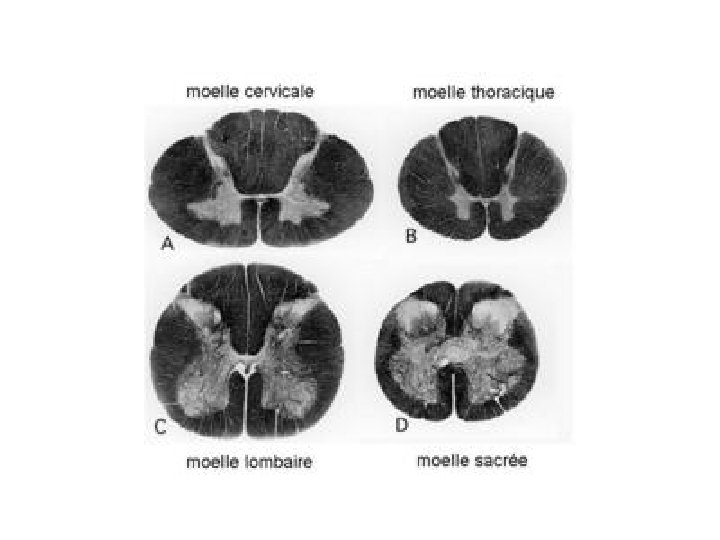

La moelle épinière va augmenter de volume de bas en haut, car les fibres qu’elle renferme y sont de plus en plus nombreuses

SUBSTANCE GRISE (SG) : v La partie antérieure « cornes ventrales » renferme les corps cellulaires des neurones moteurs Il s’agit de volumineux neurones, relais des neurones du cortex moteur

v. La partie postérieure « cornes dorsales » renferme des petits neurones sensitifs dits de 2ème ordre

Au niveau de la moelle dorsale et lombaire supérieure, il existe des « cornes latérales » où se trouvent les corps cellulaires neurones sympathiques efférents pré ganglionnaires

SUBSTANCE BLANCHE (SB) : v. La SB postérieure correspond aux « cordons postérieurs » et renferme des fibres sensitives ascendantes Ces fibres véhiculent la vibration, la proprioception et le toucher discriminatif

v. La SB ventro- latérale renferme également des fibres axonales myélinisées

Il s’agit de fibres sensitives ascendantes au niveau ventro- latéral (faisceaux spino- thalamique latéral : douleur, température et ventral : toucher superficiel) et de fibres descendantes motrices (faisceau cortico-spinal)